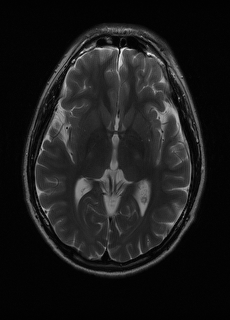

As we observe from the right image in Fig. 2, our BRM, both from MIMO and SISO settings, predicts the performance of dedicated models with a high correlation. We further choose the best three , and perform the last stage of fine-tuning accordingly to (6). A visual evaluation on real data is shown in Fig. 3. For simulated data, please refer to the Supplemental Material section.

Base on the best performing , we perceive that among , , and FLAIR, the results are best when is sampled the most. We suggest that this makes intuitive sense as images provide the best contrast out of the three sequences, which can compensate for the details lost in other images. The same observation can be made on the simulated data, where both and FLAIR show good contrast. When the time setting is changed to non-uniformity, we can see that our search for the best sampling strategy reflects the change. is sampled more as a result of faster acquisition time, while is still sufficiently sampled.

| Sequence | LR | SISO | MIMO | MIMO tuned | GT |

|---|---|---|---|---|---|

(a) 34.38/0.9371

(a) 34.38/0.9371

|

(b) 42.42/0.9883

(b) 42.42/0.9883

|

(c) 44.60/0.9920

(c) 44.60/0.9920

|

(d) 45.50/0.9940

(d) 45.50/0.9940

|

(e) PSNR/SSIM

(e) PSNR/SSIM

|

|

(f) 29.74/0.8903

(f) 29.74/0.8903

|

(g) 36.25/0.9734

(g) 36.25/0.9734

|

(h) 36.42/0.9752

(h) 36.42/0.9752

|

(i) 37.70/0.9832

(i) 37.70/0.9832

|

(j) PSNR/SSIM

(j) PSNR/SSIM

|

|

(k) 39.89/0.9311

(k) 39.89/0.9311

|

(l) 43.94/0.9864

(l) 43.94/0.9864

|

(m) 44.74/0.9883

(m) 44.74/0.9883

|

(n) 45.49/0.9894

(n) 45.49/0.9894

|

(o) PSNR/SSIM

(o) PSNR/SSIM

|